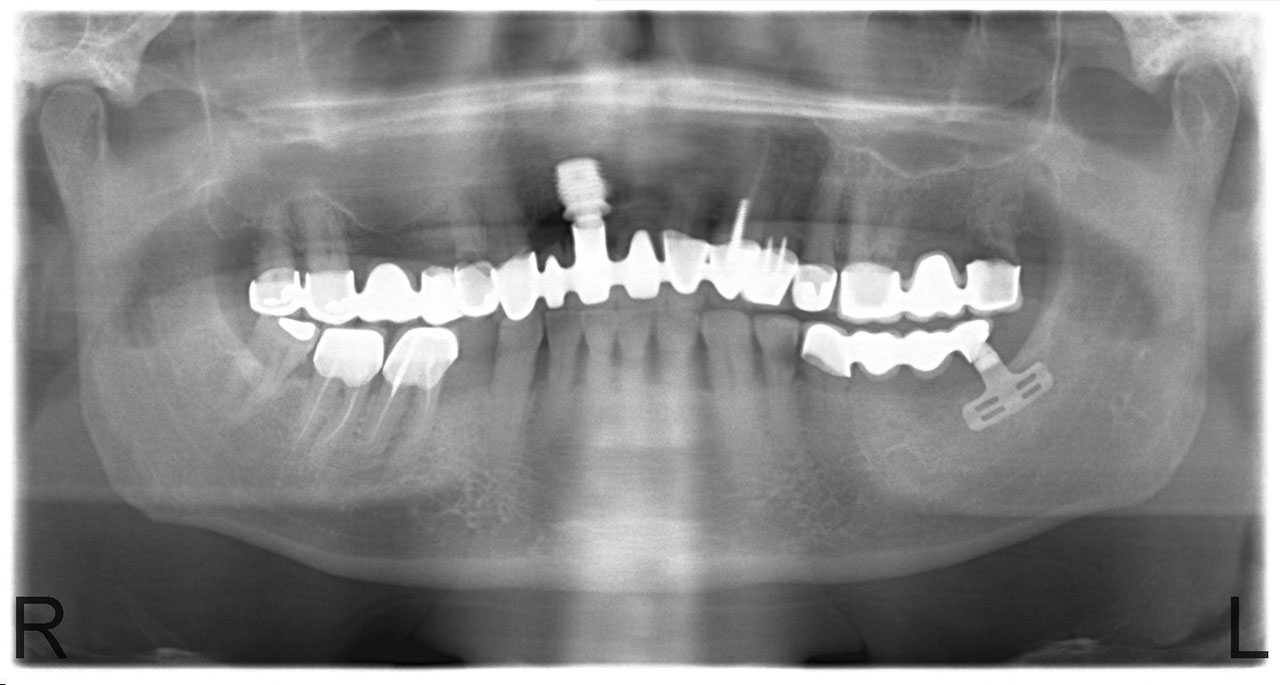

Sikerét mindenekelőtt a gyorsaságának köszönheti, hiszen a mai rohanó világban kinek van ideje, kedve fogatlanul otthon ülni heteket, hónapokat a fogpótlásra várva? Az Ihde implantációs eljárás során a páciens azonnal, de legkésőbb 72 óra múlva egy rögzített (tehát nem mozgó, nem kivehető) pótlással hagyja el a rendelőt. Ez az egyedülállóan gyors eljárás annak köszönhető, hogy azonnal tudunk implantálni szinte bárhova, akár foghúzás után is, továbbá a művelet nem jár nagy feltárásokkal, nincs szükség csontbeültetésre, így a gyógyulás folyamata is nagyon gyors és a beültetés technikájának köszönhetően maximum 72 óra múlva a korona is feltehető. Tehát ennyi idő alatt foga lesz a betegnek és az implantátum azonnal terhelhetővé is válik.

Az eljárás mellett szól az is, hogy nagyon biztonságos. A cég adatai alapján a beültetett implantátumok 98.2%-a sikeres. Az azonnali terhelésű implantátumokkal rögtön, akár foghúzás után is szinte bárhová lehet implantálni, bárkinek, legyen szó cukorbeteg, dohányos, vagy akár csontritkulásban szenvedő páciensről. Ennek köszönhető, hogy a betegek 99%-ánál alkalmazható a módszer.

Természetesen, az Ihde Azonnal Terhelhető Implantátum Rendszer alkalmazása speciális szaktudást igényel, így elengedhetetlen az orvosok gondos és folyamatos képzése. Ez, illetve a kiváló minőségű svájci alapanyagok és a sok évtizedes, precíz, innovatív gyártási technológia együttese adja, hogy a cég kiemelkedően magas (98,2%-os) sikert ér el, az Ihde implantátumok bent maradásának mérésekor.